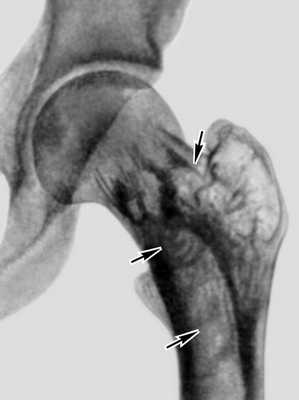

Диагноз устанавливают преимущественно на основании данных рентгенологического исследования. Ранние этапы болезни рентгенологически характеризуются изменениями внутренней архитектоники кости, затем к ним присоединяются утолщение и деформация кости. Наиболее типична для П. б. видимая на снимках груботрабекулярная перестройка костной ткани. Костные перекладины утолщаются, группируются в пучки, вследствие чего вся структура кости приобретает грубый вид, ячейки между костными перекладинами становятся крупными, неправильной формы (рис. 1), костные перекладины в основном сохраняют свою функциональную направленность. В процесс перестройки вовлекается и корковое вещество, которое приобретает волокнистый вид; в дальнейшем граница между корковым и губчатым веществом теряется, кость на уровне поражения утолщается, деформируется. Целость контуров кости всегда сохраняется. Перестраивающиеся длинные трубчатые кости постепенно искривляются (рис. 2), с выпуклой стороны нередко развиваются зоны патологической функциональной перестройки — Лоозера зоны.

Рис. 1. Рентгенограмма левого тазобедренного сустава больного с болезнью Педжета: структура межвертельной области бедренной кости имеет грубый вид, ячейки (указаны стрелками) между костными перекладинами крупные, неправильной формы.